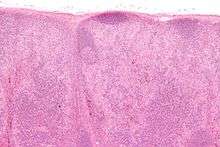

Benign (reactive) lymphadenopathy

Benign lymphadenopathy is a common biopsy finding, and may often be confused with malignant lymphoma. It may be separated into major morphologic patterns, each with its own differential diagnosis with certain types of lymphoma. Most cases of reactive follicular hyperplasia are easy to diagnose, but some cases may be confused with follicular lymphoma. There are six distinct patterns of benign lymphadenopathy:[7]

- Follicular hyperplasia: This is the most common type of reactive lymphadenopathy.[7]

- Paracortical hyperplasia/Interfollicular hyperplasia: It is seen in viral infections, skin diseases, and nonspecific reactions.

- Sinus histiocytosis: It is seen in lymph nodes draining limbs, inflammatory lesions, and malignancies.

- Nodal extensive necrosis

- Nodal granulomatous inflammation

- Nodal extensive fibrosis (Connective tissue framework)

- Nodal deposition of interstitial substance

These morphological patterns are never pure. Thus, reactive follicular hyperplasia can have a component of paracortical hyperplasia. However, this distinction is important for the differential diagnosis of the cause.